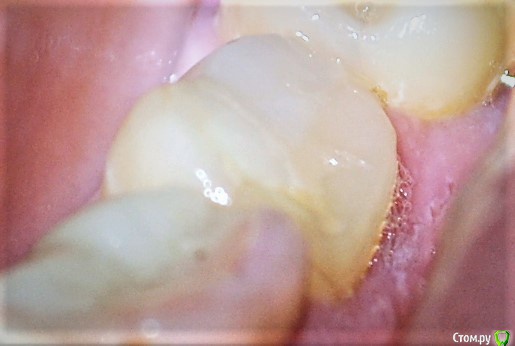

unogirlie Опубликовано 2 мая, 2017 Автор Поделиться Опубликовано 2 мая, 2017 Не сразу увидела, что кто-то написал....Вот как получилось, максимально попробовала увеличить и придать четкости. Что теперь подскажете? Ссылка на комментарий